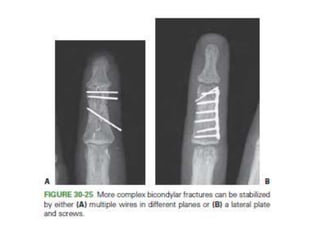

• Condylar fractures

– CRIF- converging or diverging.